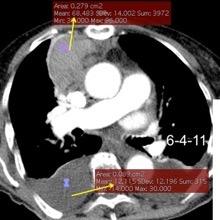

Hemorrágica………….30-70 UH

Extravasación iv. con sangrado activo……….>90 UH

“Simpático”………….,,,,<15 UH

Durso AM et al. Penetrating Thoracic Injury. Radiol Clin N Am 2015.

Urogénico……………….< 15 UH

Entérico.. ………………+/- 15UH

Biliar, Quiloso……………..<0 UH

68 UH

12UH

Abramowitz1 Y et al. Pleural Effusion: Characterization with CT Attenuation Values and CT Appearance .AJR 2008